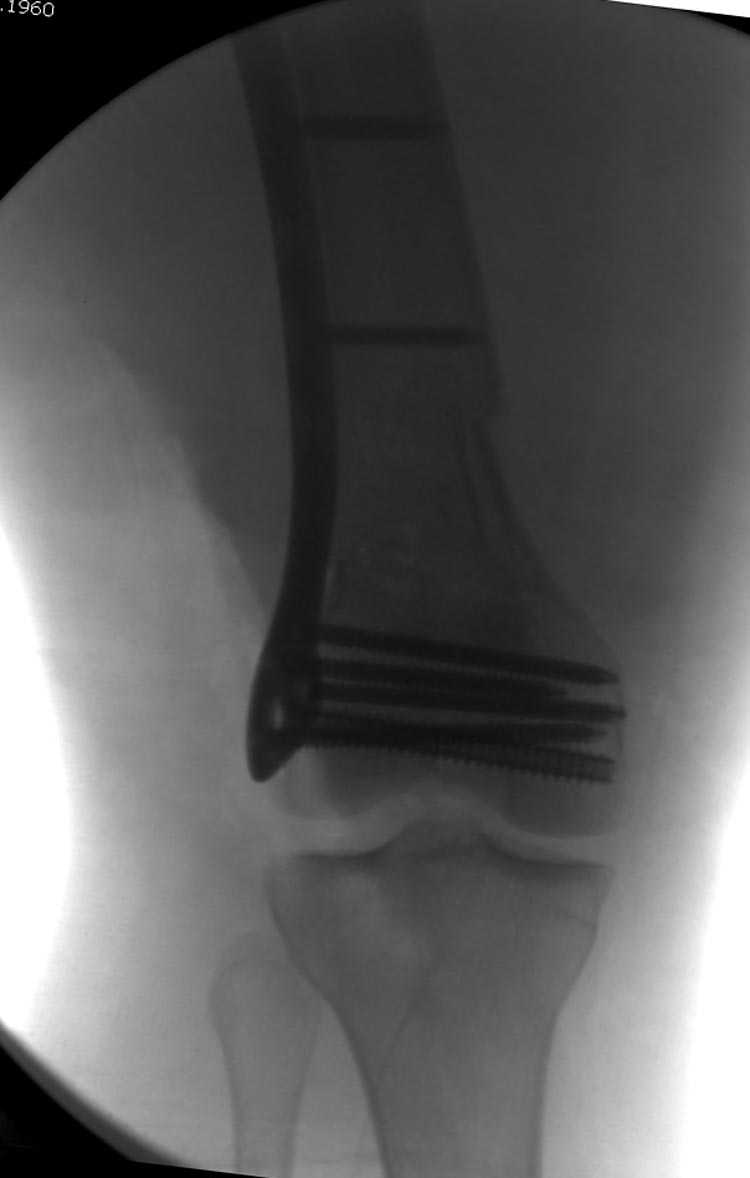

Почти все компании имеют пластины с угловой стабильностью, начиная от Stryker, Zimmer NCB и DePuy Polyaxial Plate . Если у NCB шуруп блокируется специальной шайбой, то Polyaxial Plate имеет вариабельный угол введения шурупов.

Поэтому такие меж и над- мыщелковые переломы более предпочтительным считается фиксировать мыщелковыми пластинами

Устанавливается из малого разреза "не вскрывая сустав" со стороны латерального мыщелка, и Insertion Jig позволяет установить пластину "мостовидно" перкутанно в проксимальном отделе, "не вскрывая и не трогая" место перелома.